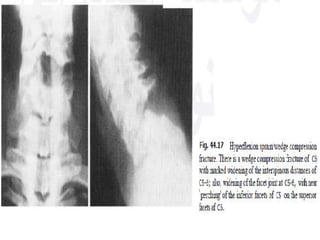

Flexion Teardrop Fracture C5-6

fracture is the result of a combination

of flexion and compression ,most commonly at C5-6

 The teardrop fragment comes from the

anteroinferior aspect of the vertebral body. The

larger posterior part of the vertebral body

is displaced backward into the spinal canal.



Best seen on lateral view

 It is an completely unstable fracture associated with

complete disruption of ligaments and anterior cord

syndrome and quadriplegia

 70% of patients have neurologic deficit.

common in MOTOR VECHICLE ACCIDENT

Signs:

Prevertebral swelling

associated with anterior

longitudinal ligament tear.

Teardrop fragment from

anterior vertebral body

avulsion fracture.

Posterior vertebral body

subluxation into the spinal

canal.

Spinal cord compression

from vertebral body

displacement.

Fracture of the spinous

process.

Fracture of

the spinous

process of

C4

Fracture of the body

of c5 with a small

fragment

anteriorly

Acute angulation at the level of C5C6

with displacement of C5 in posterior

direction